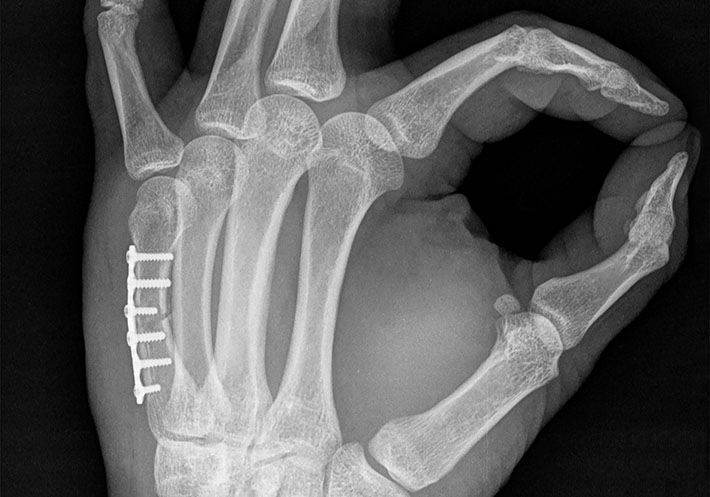

Small bone plates, as detailed in this standard, are metallic plates used to fix far extremities in the human body, like fingers, toes, and areas in the cranium and upper face.

According to ASTM member Joe Turner, this standard (F3437) provides useful test methods for plates of such a small size.

“Although standards are available for the testing of metallic bone plates, due to the smaller size of plates used in the far extremities, setup and execution of these tests can be difficult,” says Turner, engineering manager at Acuity Surgical. “Thus, this standard offers alternative test methods that are more appropriate for plates used in small bone fracture fixation.”

The standard will help address performance of these bone plates and provide a basis for their mechanical comparison.